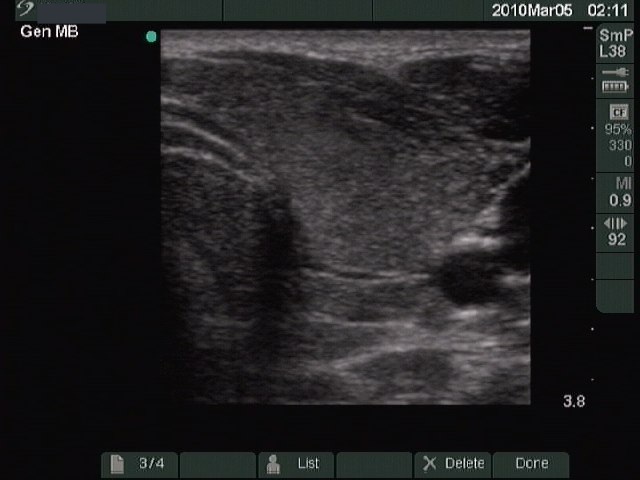

Second examination 4 months later (2nd row):

Clinical presentation: three months after discontinuation of methimazole therapy the patient had complaints suggesting recurrence of the hyperthyroidism.

Palpation: no abnormality.

Functional state: hyperthyroidism with TSH-level 0.02 mIU/L, FT4 33.1 pM/L.

Ultrasonography: the thyroids were hypoechogenic, and the vascularization was increased but not such an extent as observed at the first examination.

Clinical diagnosis: recurrent hyperthyroidism caused by Graves-Basedow's disease.

The patient was treated again with methimazole. 6 weeks later when FT4 level has normalized, the patient underwent radioiodine therapy.